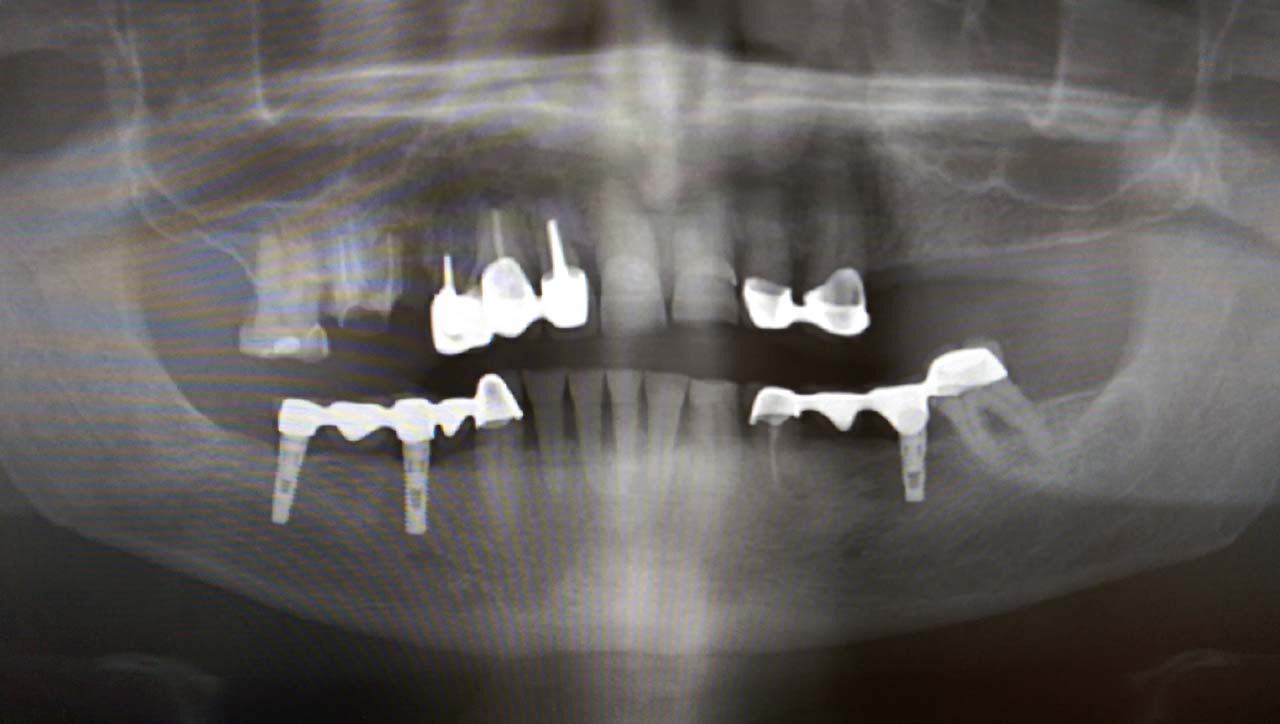

Elhanyagolt fogsor cseréje 2 nap alatt

2 nap alatt varázsoltuk ezt a szép esztétikus alsó, felső körhídat implantátumokkal megtámasztva a korábban elhanyagolt szájba. Az 1. nap 26 fogat távolítottunk el, mert annyira rossz állapotban voltak, és rögtön azonnal terhelhető IHDE svájci implantátumokat raktunk be, fentre 8, lentre 6 darabot. A sebeket összevarrtuk és intraorális szkennerrel digitális lenyomatot vettünk. 2 nap múlva pedig beragasztottuk a kész PMMA műanyag körhidakat. Dr. Kelemen Péter és a Symbion Fogtechnika munkája.